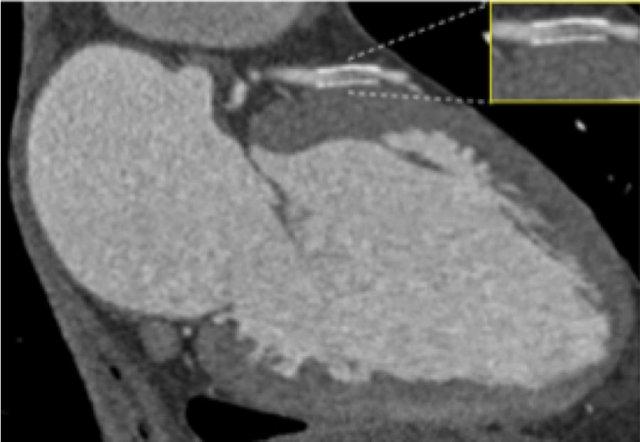

Positive remodeling

Positive remodeling is defined as a compensatory outward enlargement of the vessel wall at the site of the atherosclerotic lesion with preservation of the coronary lumen (8).

On histology plaques with positive remodeling show a higher lipid content and abundance of macrophages (9).

Patients with positive remodeled plaques can present with an acute coronary syndrome without any prior cardiac history.

An example of positive remodeling of a non-calcified plaque in the mid RCA.

There is outward growth of the plaque with minimal stenosis of the lumen.

Another example of positive remodeling of a calcified plaque in the proximal LAD.

Again, the plaque is outward from the lumen causing no stenosis in the LAD.